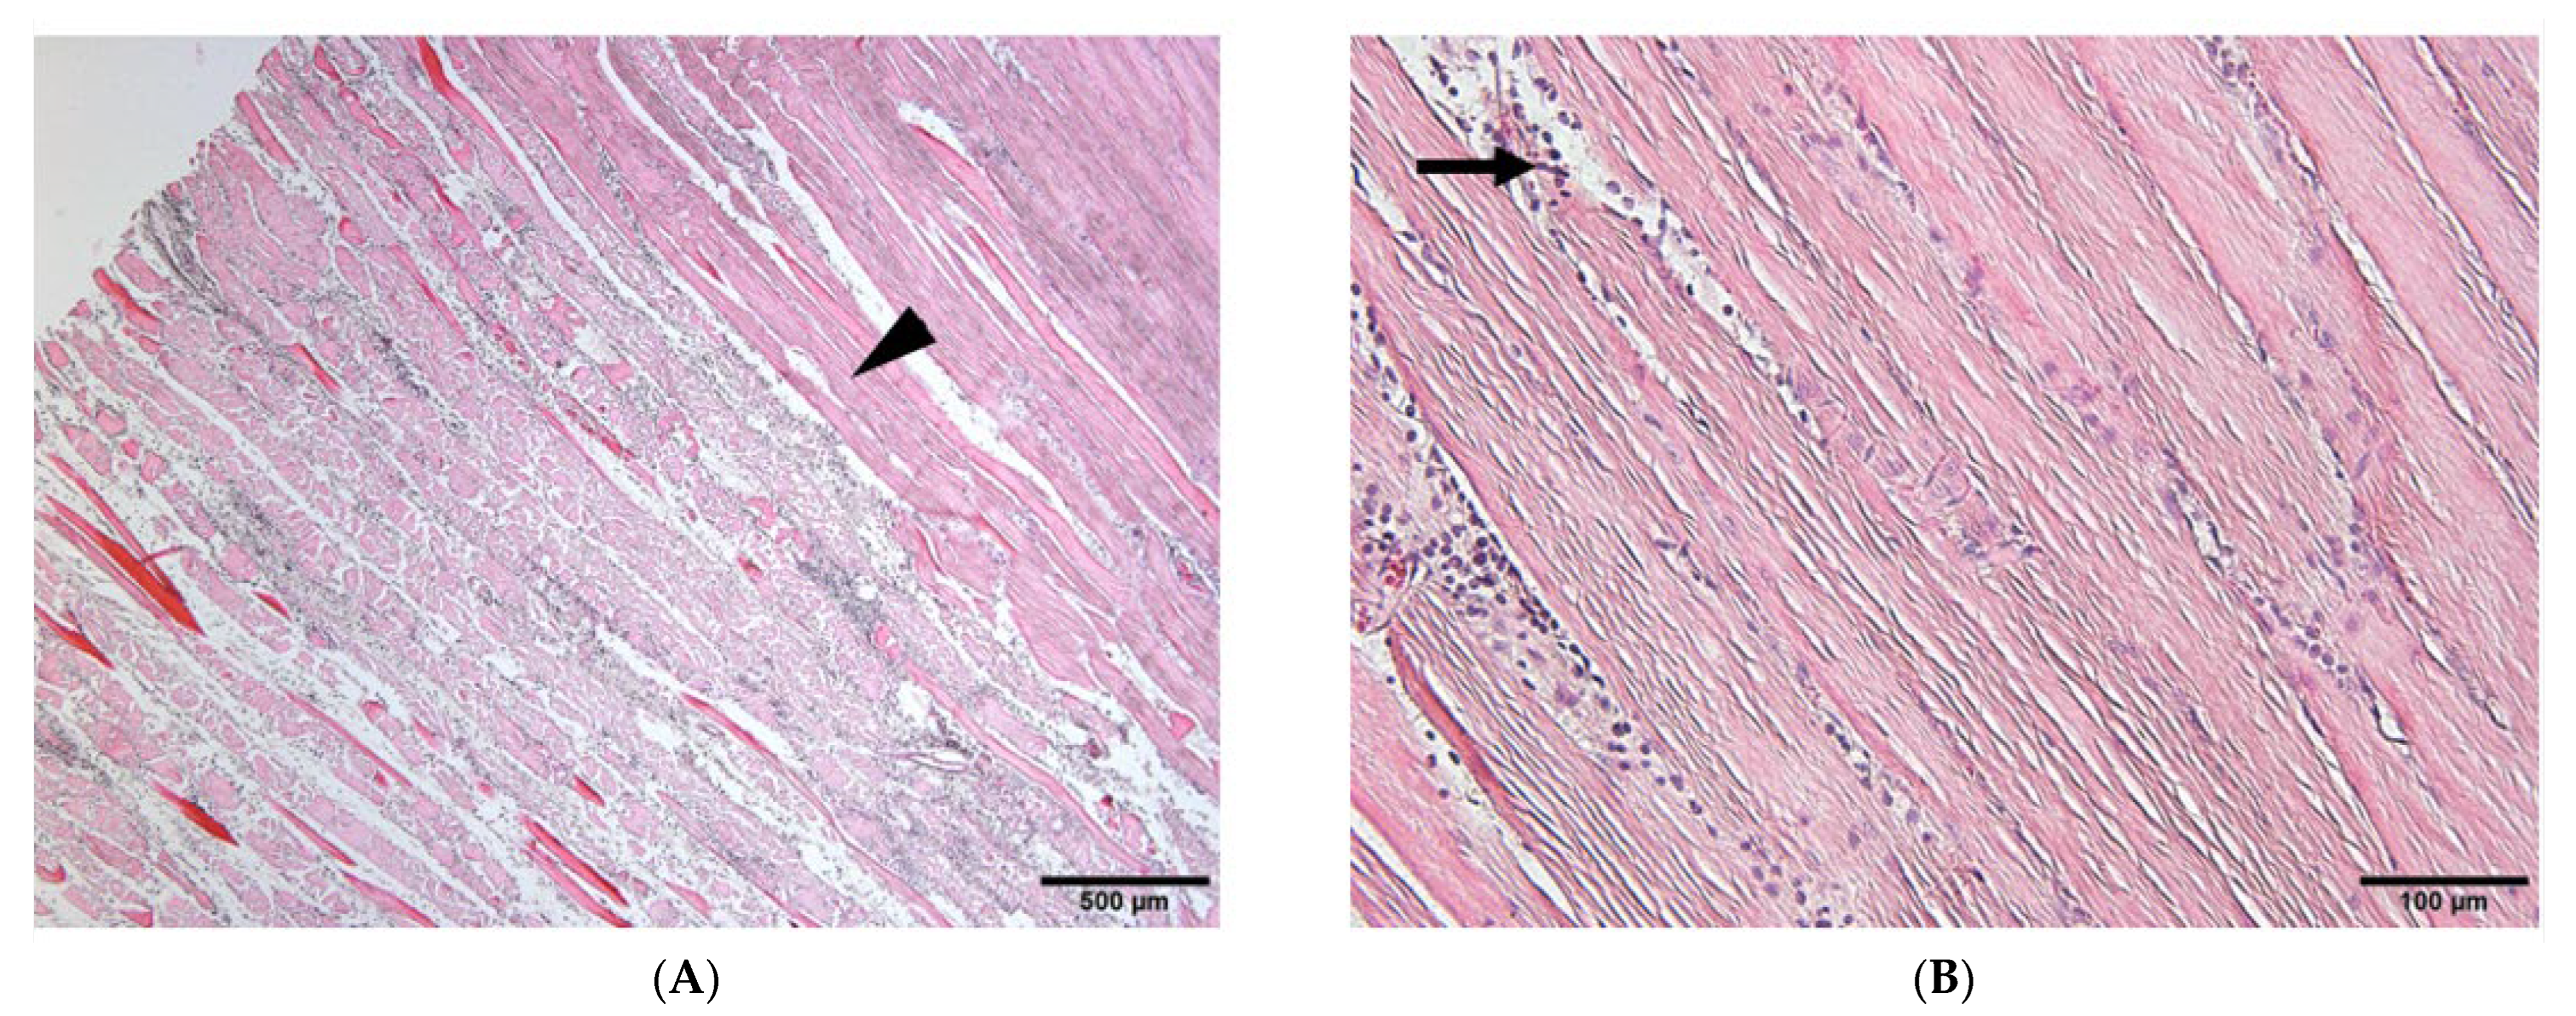

3.2. Histological Findings